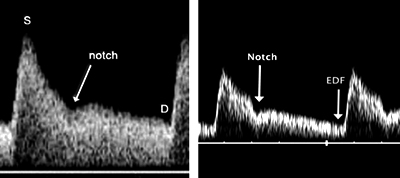

Μείωση της ροής στις μητριαίες αρτηρίες (αύξηση των αντιστάσεων), συσχετίζεται

με αυξημένη πιθανότητα εμφάνισης προεκλαμψίας και καθυστέρηση της ενδομήτριας

ανάπτυξης.

Αύξηση των αντιστάσεων στις μητριαίες αρτηρίες στην 24η εβδομάδα κυήσεως, ανευρίσκεται

σε ποσοστό 5% των κυήσεων όπου πραγματοποιείται έλεγχος ρουτίνας.

Το παθολογικό Doppler συσχετίζεται με την εμφάνιση βαρείας προεκλαμψίας και

η ευαισθησία της μεθόδου είναι κοντά στο 75%, ενώ αναφαίνεται με την αύξηση

των αντιστάσεων και την παρουσία κομβίων (notch) στην απεικόνιση της κυματομορφής.

![]() |

|

| Εικόνα 10. Παθολογικά Doppler μητριαίων και ομφαλικών αρτηριών | |